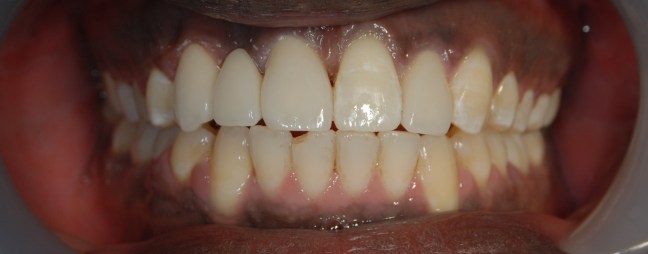

Kozmetikai kezelés: régi tömött, szuvasodott frontfogak szanálása, koronával történő leplezése, megsüllyedt harapás korrekciója.

A választott korona típusa: E-max préskerámia (fémmentes) és cirkon szóló koronák kombinációja.

A választott fogszín A1 .

A protetikai munka elkészülésének ideje: 5 munkanap.